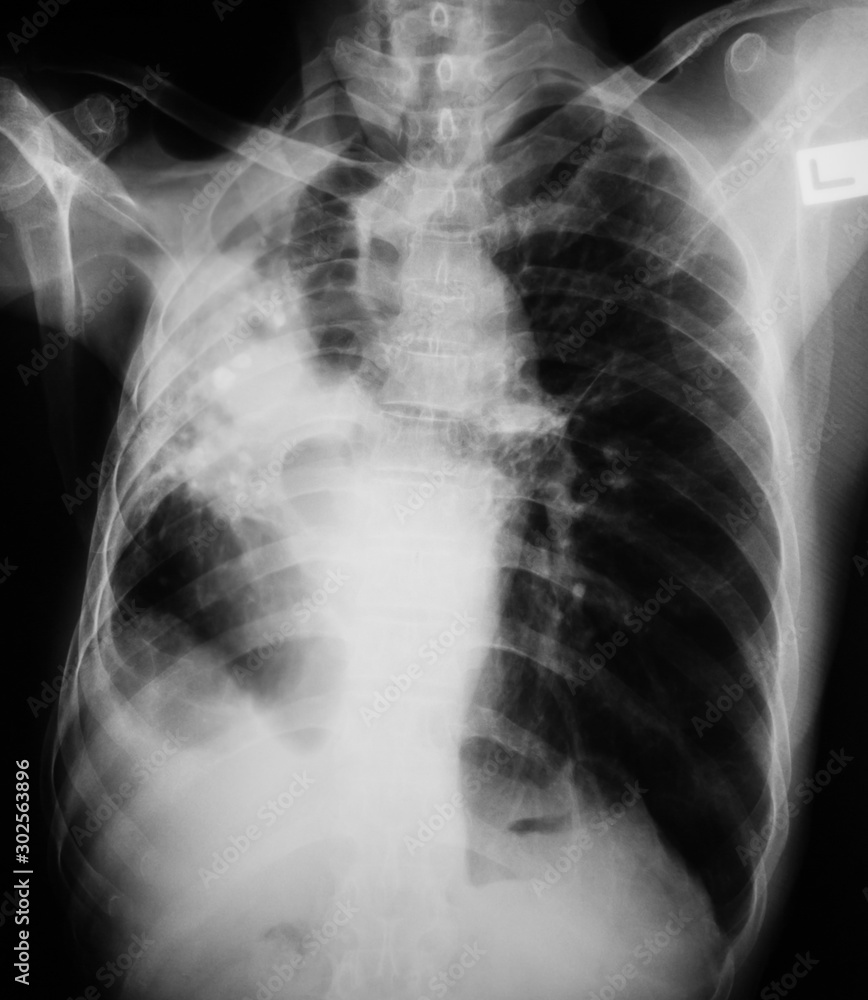

What Does Tb Look Like On Chest X Ray . There are no radiological features which are in themselves diagnostic of primary mycobacterium tuberculosis infection (tb) but. Your health care provider will do other tests to determine if you have inactive tb or active tb. A positive test result for tb infection means you have tb germs in your body.

A positive test result for tb infection means you have tb germs in your body. Your health care provider will do other tests to determine if you have inactive tb or active tb. There are no radiological features which are in themselves diagnostic of primary mycobacterium tuberculosis infection (tb) but.